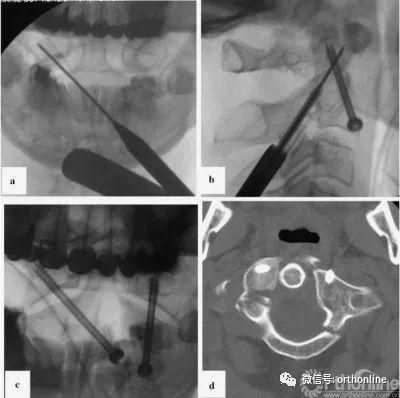

在双平面x线引导下,将K-wire穿过C2椎体下边缘并插入寰椎对侧侧块(图3a),并用其钻通骨隧道。在骨隧道中插如一根空心皮质内固定螺钉(直径4mm,长度38mm),螺钉头在C2椎体的位置有利于左侧关节的Reindl固定。然而,C2双侧侧块明显变薄(CT数据;图1,右)使得我们无法实施这种方法。

在使用Halo架的同时,将患者翻身至俯卧位,采用标准技术用直径4mm、长度40mm的空心皮质内固定螺钉进行左侧单侧经关节固定[7](图3 b)。x线图像及CT对照数据见图3c,d。在术后拆除Halo架。

图3

图3病例1:固定时x线及对照CT扫描;a、使用对侧轨迹将克氏针置入右侧侧块;b、左侧单侧后路经关节固定;c、开口位x线;d、置钉后的三维CT扫描图片(轴位);螺钉位于寰椎两侧的侧块,左侧为双皮质;CT,计算机断层扫描

First, we used the Halo device for head fixation whilst the patient was in the supine position. One of the Halo pins was placed according to the location of the skull fracture and skin wound. For this reason, we fixed the Halo using only three pins, which allowed us to reposition appropriately and achieve immobilization during surgery. Reduction of the vertical atlantoaxial dislocation was performed using traction. Skin incision for contralateral screw insertion was planned using transoral radiography. A K-wire was attached according to the screw insertion trajectory. The intersection between the K-wire line and the medial edge of the sternocleidomastoid muscle indicated the midpoint of skin incision. The left anterior bar of the Halo device was temporally removed to facilitate approach performance during contralateral fixation. The left transcervical approach to the base of the C2 vertebra was performed through a 2cm skin incision. A port for the cannulated instrument was placed near the lower edge of C2, 5mm lateral from the midline. K-wire was inserted through the lower edge of C2 into the opposite lateral mass of the atlas under two-plane X-ray control (Fig.3a). This K-wire was used for bone tunnel drilling. A cannulated self-tapping cortical lag screw (4mm in diameter and 38mm in length) was inserted through this tunnel. The position of the screw head in the C2 vertebra facilitated fixation of the left lateral joint using the Reindl method; however, significant, bilateral thinning of the anterior lip of the C2 lateral mass (CT data; Fig.1,right) prevented us from using this technique. While using the Halo device, the patient was subsequently turned over into the prone position, and a left-sided unilateral transarticular fixation using a cannulated self tapping cortical lag screw (4mm in diameter and 40mm in length) was performed using the standard technique[7] (Fig.3b). Control X-ray images and CT data are provided in Fig.3c, d. Following surgery, the Halo device was removed.

Fig. 3 Case 1: X-ray images of the fixation stages and control CT scan. a K-wire insertion into the right lateral mass using a contralateral trajectory. b Left-sided unilateral posterior transarticular fixation. c Control X-ray in the transoral plane. d CT scan control after screw insertion (axial plane). Screws are located in the lateral masses of the atlas on both sides and are bicortical on the left side. CT computed tomography